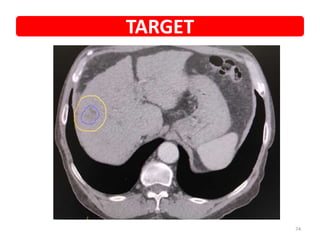

• Diagnosis • Hepatocellular carcinoma

• PET • Small lesion in segment 7

• Planned SBRT • 45Gy/3#

• PET POST SBRT 3M • Complete resolution

TARGET

• NAME • UMR •Diagnosis • Hepatocellular carcinoma • Presented with • Diagnosed during screening • PET • Small lesion in segment 7 • Planned SBRT • 45Gy/3# • PET POST SBRT 3M • Complete resolution • Now • f/up • COURTESY • DR VKR Case details 72